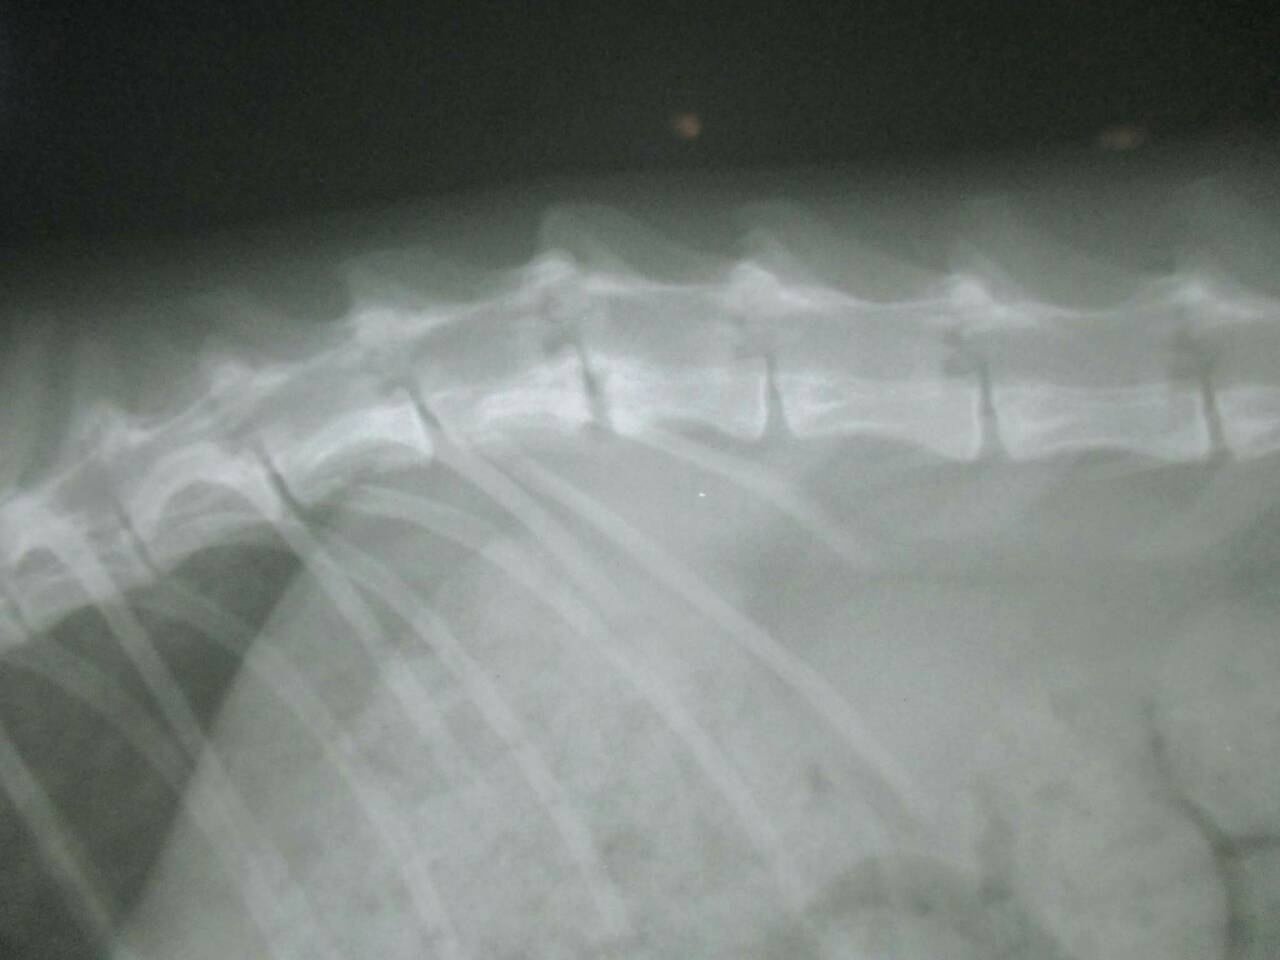

主題: 壽山收容所 背傷癱瘓貓 申請者姓名: 劉素鳳 花色: 申請日期: 2016-02-02 23:46:43 申請者部落格: 申請者臉書網址: https://m.facebook.com/sufeng.liu?ref=bookmarks 所在縣市/合作醫院: 高雄市/樂生動物醫院 治療費用: 3200元 需求人數: 8人 已結案 (2024-06-01 13:41:09) 報名人員: Freesia Tsai(已付款)、Amber Chung x2(已付款)、兔子(已付款)、karena(已付款)、Nancy Wu(已付款)、Tina Chen(已付款)、吳金英(已付款)、 候補人員: 動物病情說明: 壽山收容所專案的貓咪,這隻三花貓小刀 原本背部傷口有在癒合了,但在前一家醫院觀察後發現他後軀的神經反射有問題,後腳目前是都無法站,而且有點癱瘓的狀況,只能靠前肢撐著。

醫生初步檢查左邊腸薦關節有做手術,胸腰椎交接處(T13~L1)有受傷,可能是造成後驅癱瘓的主因,左右兩側後腳還有反射但左邊反應較差,傷口部分目前還好並無分泌物但後面幾天還是需觀察,如有分泌物出現則有可能又需做清創手術,血檢並未有異常,貓咪目前食慾還不錯,所以並未上點滴,目前會先就傷口照護為主, 醫生建議貓咪轉到大醫院做針灸的治療,努力應該會有康復的機會, 謝謝大家幫助這貓咪^^ . 、